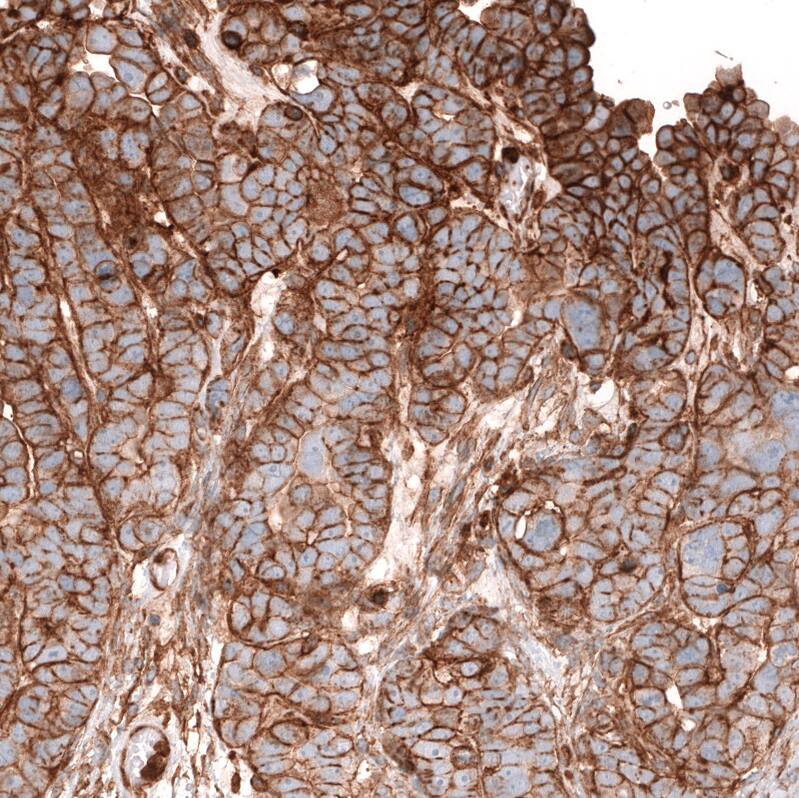

Staining of human ovarian cancer (papillary carcinoma) shows strong membranous positivity in tumor cells.